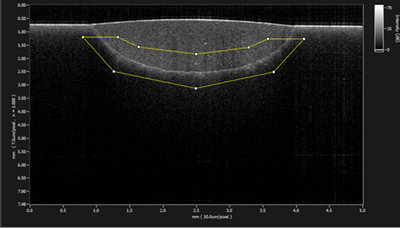

① 3D波長走査型光干渉断層計を使用した研究

光干渉断層計(OCT)は近赤外光を用い、生体の断層画像を非侵襲的に得ることができます。中でも波長走査型OCT(SS-OCT)は画像深度が深く、画像処理速度も速いことから、う蝕の診断や修復物の適合性の評価など、保存修復領域における有用性が高いと考えられます。

3.う蝕原性バイオフィルムの評価

う蝕の発生に関与するバイオフィルムの形成過程を理解することは予防歯科において重要である。本研究では、in vitroで培養したう蝕原性バイオフィルムをSS-OCTで解析し、その厚さや構造を非侵襲的に定量評価した。従来は破壊的手法に依存していたバイオフィルム研究に新たなアプローチを提供し、う蝕予防研究の発展に貢献すると考えられる。

<参考文献>

Tabata T, Nakagawa H, et al. Arch Oral Biol. 2024;165:106009.